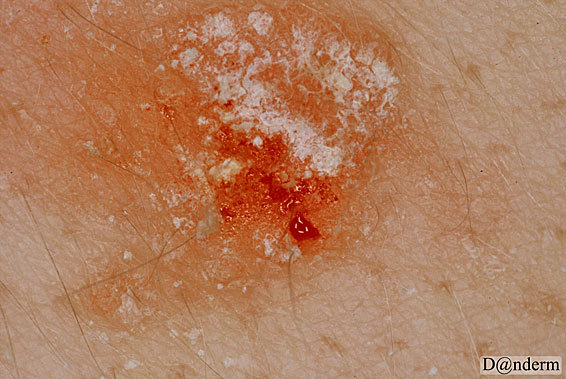

What is Auspitz sign?

Scratching/removal of psoriatic scales causes capillary bleeding